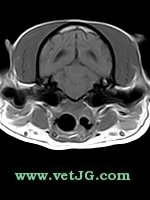

RESONANCIA MAGNÉTICA

AXIAL